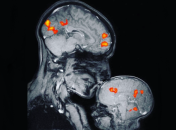

Исследования показывают: младенцы, даже не глядя, различают дотрагивания незнакомца и своего родителя.

Считается, что объятия полезны для здоровья. Для этого психологи рекомендуют обниматься 8 раз в день.

Объятия, как и смех, эффективны при лечении различных недугов, а также помогают избавиться от депрессии и стресса.

Врачи уверяют, что объятия родителей способствуют лучшему развитию ребенка.

Объятия укрепляют иммунную систему человека.

Ощутимая социальная поддержка сводит к минимуму риск заражения инфекцией.